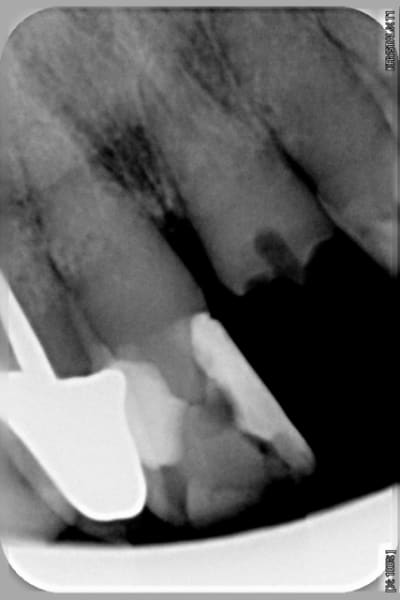

je vous met les radios de 2003 faites par mon prédécesseur

les radios de 2009

Sur la radio, perte osseuse sur les centrales, c'est quand même assez facile à voir, ensuite, surdose de compo, ça doit être très joli..j'imagine les autres dents, s'il en reste.

> Sur la radio, perte osseuse sur les centrales, c'est quand même assez facile à

d'ailleurs on le voit sur la radio que j'ai postée, il y a un début de voie d'accès

et puis j'ai commencé à me demander ou j'allais, aucune lumière canalaire visible, ni en bouche, ni à la radio, une racine pas très longue...